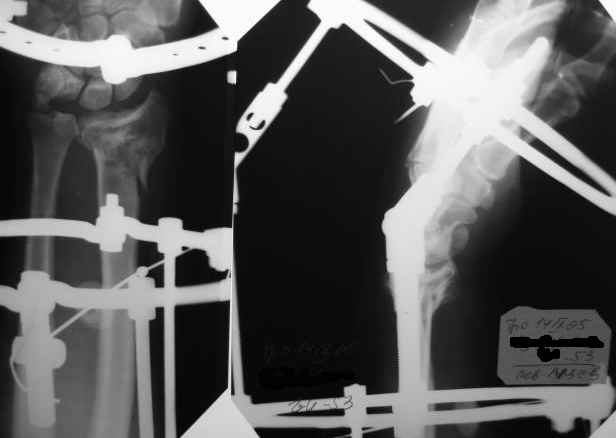

Спасибо, коллеги, за помощь в принятии решения. Остановились на АВФ, но в классической компоновке (3 секционный, замкнутые кольца). Снимки конечного результата в приложении.

Интраоперационно старались добиться более лучших взаимоотношений, но выяснилось (благо больной под региональной анестезией!), что у пациента был <перелом луча> с обеих сторон около 20 лет назад, движения на оперируемом суставе были несколько ограничены. Поэтому решили оставить так. К сожалению, снимков 20-ти летней давности не нашли. Планирую оставить внешнюю фиксацию на весь срок. Жду комментарии. С уважением, А.Минервин.

Все получилось хорошо, положение отломков более чем премлемое.

Абсалютное показание к внеочаговому дистракционному остеосинтезу аппаратом Илизарова за пястные кости. Судя по рентгенограмм :

Полифрактура. Откр. внутрисуставной оскольчатый перелом дистального конца лучевой кости и перелом шиловидного отростка и диафизарный перелом локтевой кости со смещением костных отломков. Для достижение идеального устранение смещений костных отломков (что очень важно для дальнейшего воостановление функции лучезапстного сустава) предлагаю по новой методики нашей клиники.

По рентген у луча "минус" вариант и это отрицательно будет высказываться на функции лечезапятсного сустава, т.е. у больного ограничение локтвеой девиации кисти.